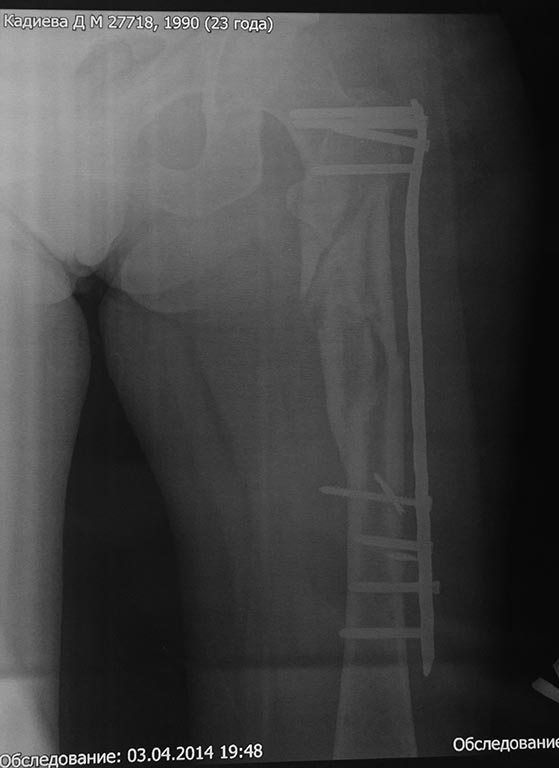

Пациентка К., 23 л., красивая девушка, уроженка одного из удаленных южных регионов России. Травма 31.12.13 в результате ДТП (столкновение а/машин). Находилась на лечении в нашем травматологическом отделении со следующим диагнозом: Сочетанная травма: ОЧМТ: Ушиб головного мозга легкой степени. Перелом передней стенки лобной пазухи со смещением отломков. Перелом латеральной стенки левой орбиты без смещения отломков. Ушибленные раны левого верхнего века. Ушиб левого легкого. Закрытое вертикально-нестабильное повреждение таза: трансфораминальный перелом крестца слева, частичный разрыв левого крестцово-подвздошного сочленения, вертикальный оскольчатый перелом крыла левой подвздошной кости со смещением отломков, поперечный перелом левой вертлужной впадины без смещения отломков. Закрытый многооскольчатый перелом левой бедренной кости в в/3 и с/3 со смещением отломков. Травматический шок II ст. При поступлении (снимок): АВФ типа "передняя рама" на кости таза с блоком на бедренную кость,ПХО ран. Лечение в условиях реанимации. По приказам о травмцентрах таких пациентов мы должныотправлять в травмцентр I уровня (областная больница). Однако с некоторых пор все разговорытам о переводе (стыдно за коллег) начинаются со слов: "А железку он(она) купит?" и озвучивается родственникам сумма с 4-5 нулями. Пациентка и ее родители к состоятельным не относятся. Поэтому дальнейшее лечение проходило у нас. Кости таза фиксированы канюлированными винтами и АВФ. Предполагался БИОС бедренной кости, однако из-за отсутствия в больнице современных имплантов(угадайте с 3-х раз- почему?)и средств у больной был выполнен 22.01.14 малоинвазивный остеосинтез проксимального отдела бедра чем Бог послал (каким-то чудом оказавшаяся у нас дистальная бедренная пластина "Деост", не б/у) (см. снимки)-критика принимается. П/операционный период гладкий. Выписана с рекомендацией начать нагрузку на конечность через 12 недель после операции. Убыла на малую родину. Дальнейшая связь поддерживалась по e-mail. Рекомендации она не соблюдала: нагрузку на ногу начала недели 3 назад. Сейчас беспокоят боли в одноименном коленном суставе, отека нет, болей в месте перелома нет, анализы в норме, незначительное ограничение движений в ТБС. По месту жительства выполнила КТ (снимки и описание в приложении). Местные коллеги утверждают, что необходимо сделать реостеосинтез, но сами не берутся. Вопрос больше от пациентки: "Делать ли повторную операцию сейчас, или некоторое время походить с полной нагрузкой и сделать контроль, а там решать?"

Что здесь хорошего? Репозиции нет, в боковой проекции угловое смещение. Пластина не прилегает к кости, и хотя она блокированная, но посмотрите – внизу пластина держится всего на одном блокирующем винте, два других не состоятельны, так как один недокручен(либо уже вышел из гнезда в пластине из за нестабильности), а другой закручен не перпендикулярно пластине (да и судя по боковой проекции, даже не в своё посадочное гнездо), следовательно, блокировка ненадёжна. Кортикальный (длинный) винт не всчёт, так как не притягивает пластину к кости. Ко всему ещё и два сломанных сверла… Вероятнее всего её ждёт перелом пластины и/или миграция фиксатора. На бедре особенно часто ломают пластины… Кроме блокированного интрамедуллярного остеосинтеза ( оптимальный способ), подошли бы: 1. Открытая репозиция, нормальный остеосинтез этой пластиной. 2. Открытая репозиция, остеосинтез четырёхгранным стержнем ( которых у всех в изобилии), дополненный серкляжной фиксацией отломков.

Я так понимаю "разрушить до основания, а затем..." Четырехгранный? При таком коротком проксимальном фрагменте??? Еще и серкляжи? Браво! В дистальном стоят 4 винта (хотя согласен, что пластина несколько коротковата). Угловых смещений я на этих снимках не увидел. А "ободрать" кость открытым методом, поимете проблемы. Михаил! Было бы неплохо посмотреть не КТ, а обычные рентгеновские снимки, на них мозоль видна лучше. И если уж переделывать (хотя я своего мнения не меняю), то только малоинвазивно ЗИМО у Александра Николаевича, тем более, что отозвался помочь.